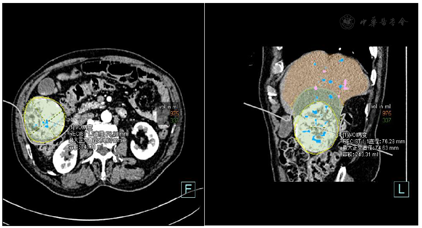

肝脏形态尚可,肝Ⅴ-Ⅵ段见一类圆形稍低密度肿块,边界尚清,内密度欠均匀,增强扫描病灶明显不均匀强化,其强化程度与腹主动脉相仿,内见低密度不强化灶,静脉期及延迟期病灶密度减低,呈快进快出表现。

三维容积分析RECIST肝脏总容积1311.68ml,左叶体积约374.8ml,右叶体积约936.81ml;病灶直径76.28mm,最大正交直径74.63mm,容积243.31ml,虚拟手术2cm安全距离内容积约:337ml(虚拟手术切除容积),2cm安全距离外容积约:975ml(虚拟手术剩余肝容积)。

诊断意见:肝Ⅴ-Ⅵ段占位,考虑原发型肝癌可能性大。